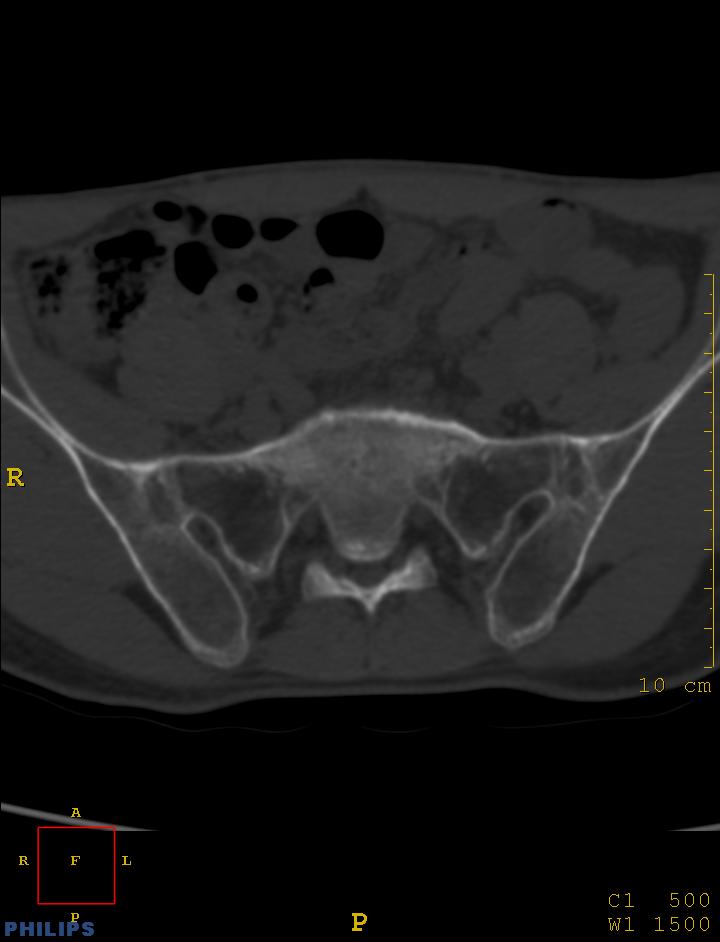

标题: CT14032:M34Y,双侧骶髂关节

m,34岁,腰痛三年,腰椎活动度明显减低,x片示腰椎竹节样改变

双侧骶髂关节面融合;强直脊柱炎

双侧骶髂关节骨性融合,软骨下囊性变,结合脊柱竹节样改变,典型的强直性脊柱炎。